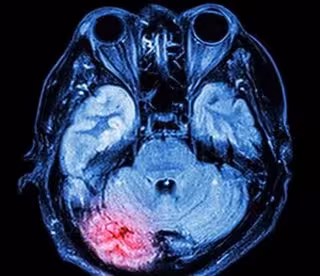

La zona roja muestra el lugar donde se inflama el cerebro después de una conmoción cerebral.

La zona roja muestra el lugar donde se inflama el cerebro después de una conmoción cerebral. - UNIVERSITY OF SOUTH AUSTRALIA